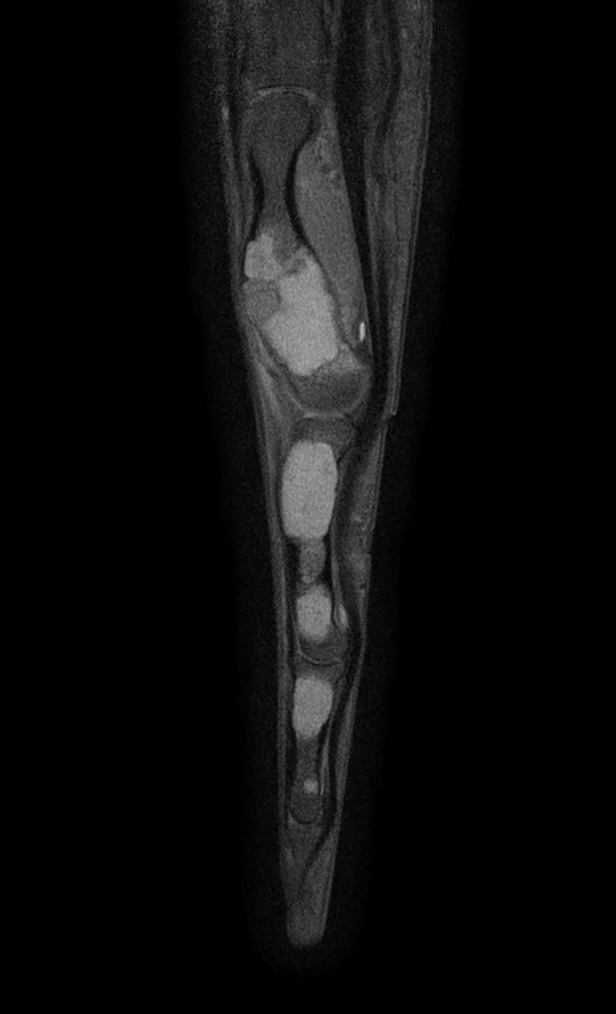

Sagittal T1w mDIXON XD TSE (Water only) (with gado)

Sagittal T1w mDIXON XD TSE (In Phase) (with gado)

Sagittal T1w mDIXON XD TSE (Partial FatSat) (with gado)